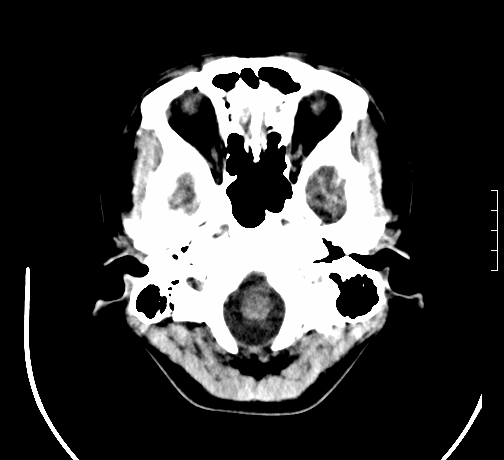

女,28岁,幼时有癫痫,常有发作,服药后可几月不发作,走路不稳3-4月,加重一月。

小脑发育畸形?

小脑萎缩。

考虑小脑发育不良,建议mri检查。

患者出现走路不稳是近几个月的事,而癫痫则有幼时就有,常发,则会常服药,癫痫药可引起小脑综合症,小脑萎缩,而小脑发育不良的主要症状不是癫痫

考虑癫痫,长期间断发服抗癫药,导致小脑综合症,小脑萎缩

不知现在还有没有癫痫,应该另有致痫灶,进一步检查。

考虑小脑发育不良伴小脑萎缩,建议mri检查。

小脑萎缩,原因待查,建议mri检查。

考虑小脑发育不良伴小脑萎缩,建议mri检查

考虑药物性小脑萎缩